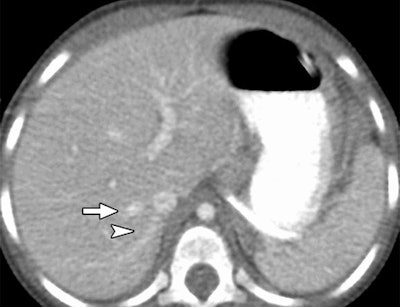

Reduced-dose axial CT images reconstructed with MBIR (above) and 100% ASIR (below) in a 30-month-old girl with a history of a malignant germ cell tumor in the right hepatic vein (arrow) and an accessory right hepatic vein (arrowhead). Images republished with permission of RSNA from 10.1148/radiol.13130362, October 3, 2013.